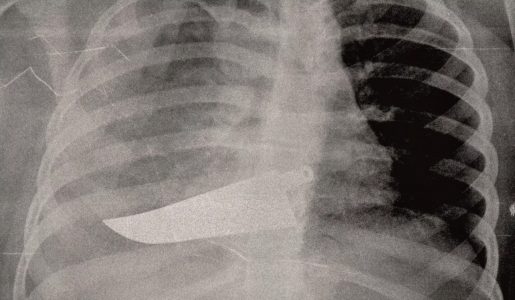

Τον Φεβρουάριο του 1930 διαγνώστηκε ότι έπασχε από σχιζοφρένεια με αποτέλεσμα να την μεταφέρουν, παρά τη θέλησή της, σε ένα σανατόριο στην Ελβετία όπου ανέλαβε να την «κουράρει» ο ίδιος ο Ζίγκμουντ Φρόιντ, ο οποίος έσπευσε να αποδώσει την κατάστασή της σε σεξουαλική διαταραχή. Αποφάσισε, οπότε, να της προκαλέσει πρόωρη εμμηνόπαυση, δίνοντας εντολή να την υποβάλουν σε ηλεκτροσόκ και να βομβαρδίσουν τις ωοθήκες της με ακτίνες Χ ούτως ώστε να αφανίσουν τη λίμπιντό της.